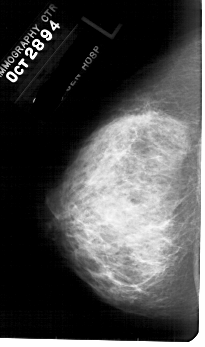

A_1781_1.RIGHT_MLO

RIGHT_MLO LINES 5491 PIXELS_PER_LINE 3256 BITS_PER_PIXEL 12 RESOLUTION 43.5 OVERLAY